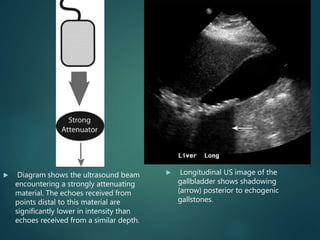

 Diagram shows the ultrasound beam

encountering a strongly attenuating

material. The echoes received from

points distal to this material are

significantly lower in intensity than

echoes received from a similar depth.

 Longitudinal US image of the

gallbladder shows shadowing

(arrow) posterior to echogenic

gallstones.